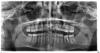

сергей2012 Опубликовано 14 декабря, 2012 Поделиться Опубликовано 14 декабря, 2012 Сегодня сделал снимок, подскажите все ли в порядке на нем?Спасибо за ответы!!!!) Ссылка на комментарий

Scrabble Опубликовано 14 декабря, 2012 Поделиться Опубликовано 14 декабря, 2012 (изменено) Орто для понимания общей картины полезно(то есть посмотреть, какие зубы невитальные, есть ли ретинированные зубы, суставы видно чуть-но не всегда) Для диагностики кариесов и состояния пародонта полезнее прикусные, для оценки периапексов-прицельные. Так вроде всё нормально. Прицельный снимок невитального 36 сделайте, чтобы детально посмотреть. Как минимум, 36 нуждается в ревизии каналов, вкладке и коронке. Изменено 14 декабря, 2012 пользователем Scrabble 1 Ссылка на комментарий

DmitrySH Опубликовано 14 декабря, 2012 Поделиться Опубликовано 14 декабря, 2012 На зубах 16, 15, 14 похоже есть кариозные полости. Но по данному снимку утверждать не могу. 2 Ссылка на комментарий